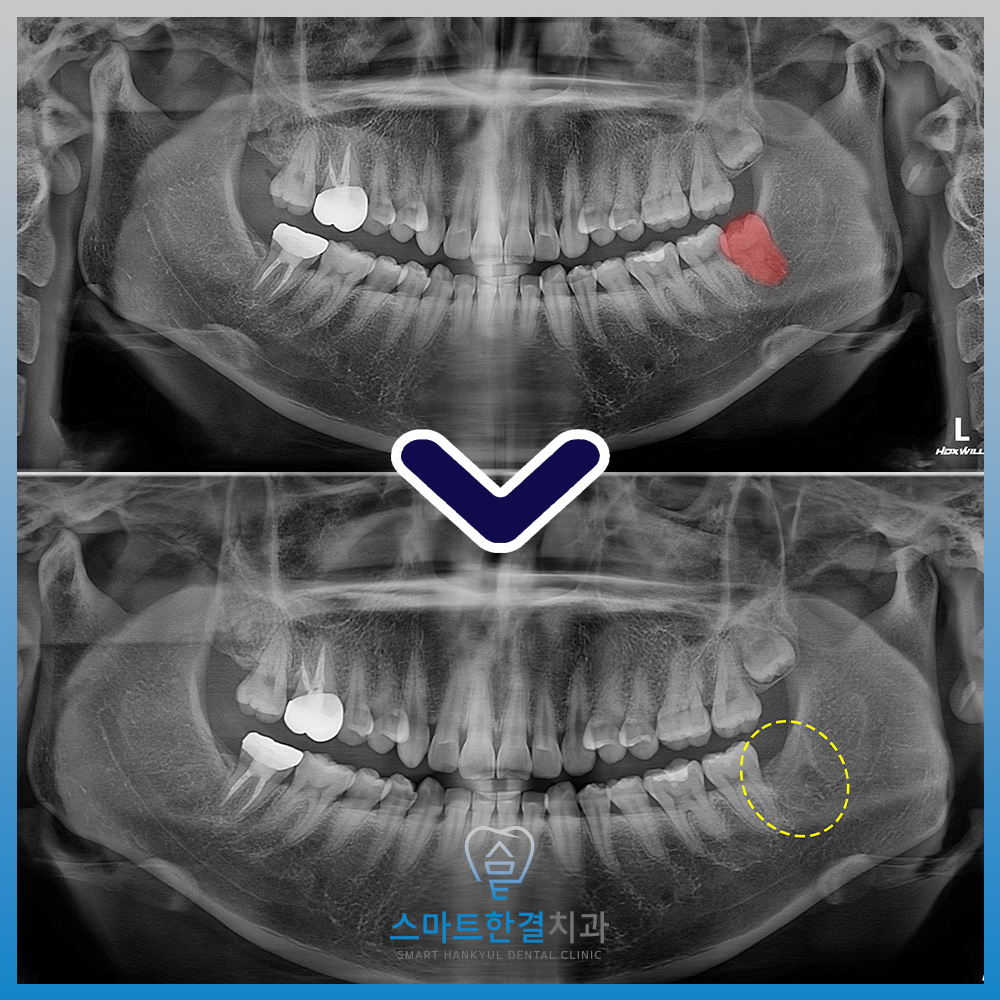

스마트한결치과의

수원사랑니 발치 전후 사진이에요.

환자분께서는 경구피임약을

복용 중인 상태에서

발치를 진행해도 되는지에 대해 걱정하셨으나,

본원에서 안내드린 발치 진행 방법과

주의사항에 대해 설명을 들으신 후

안심하신 모습을 보이셨는데요.

이후 약물 중단 후

안정적으로 발치를 진행할 수 있어

다행이라며 전반적인 치료 과정에 대해

만족감을 표현해 주셨어요.